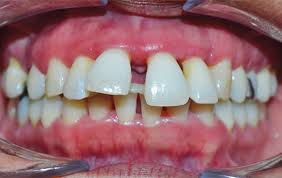

mesa de trabajo 4

Periodontitis Avanzada

En las fases más incipientes de estas enfermedades el tratamiento es un curetaje, con el que se raspa y alisa la raíz del diente y se elimina la placa bacteriana y el sarro de las bolsas periodontales.